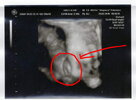

wow też czekam juz na to usg, jak bedzie widać taką dzidzie :-)

To jest coś niesamowitego

Do tej pory myślałam że dzidziuś tam sobie tylko pływa i od czasu do czasu machnie rączką. To było prawdziwe zaskoczenie kiedy zobaczyłam, że szaleje tam jak na niezłej imprezie

Nie przestawał się ruszać i podskakiwać, wreszcie się popłakałam ze wzruszenia, zresztą pewnie jak dużo kobiet kiedy pierwszy raz patrzą na swoje dziecko. Niesamowite przeżycie